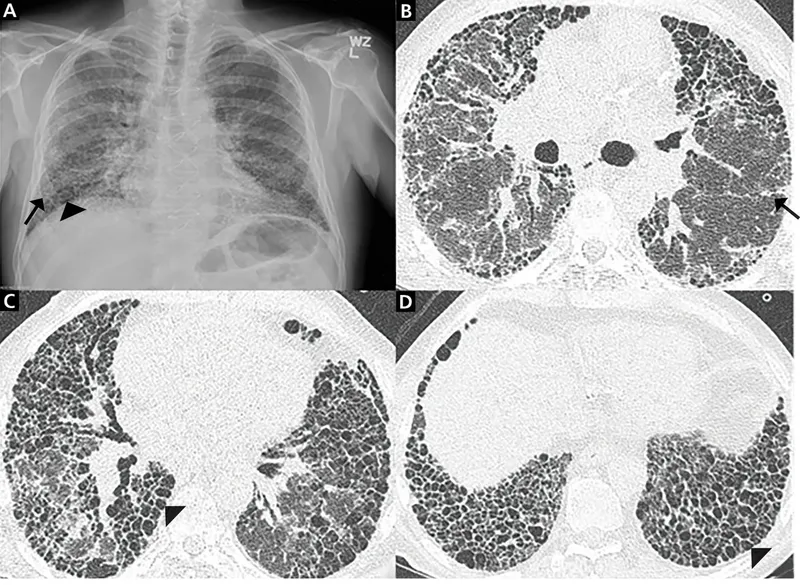

- ⚠️ Pulmonary Fibrosis: Dose-limiting, often irreversible. "Bleomycin lung."